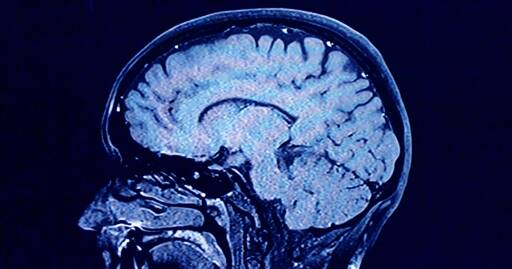

During each of these phases, our brains show markedly different characteristics in brain architecture, according to the new findings.

As we age, the human brain rewires itself. The process happens in distinct phases, or “epochs,” according to new research, as the structure of our neural networks changes and our brains reconfigure how we think and process information.

For the first time, scientists say they’ve identified four distinct turning points between those phases in an average brain: at ages 9, 32, 66 and 83. During each epoch between those years, our brains show markedly different characteristics in brain architecture, they say.

The findings, published Tuesday in the journal Nature Communications, suggest that human cognition does not simply increase with age until a peak, then decline. In fact, the phase from ages 9 to 32 is the only time in life when our neural networks are becoming increasingly efficient, according to the research.

During the adulthood phase, from 32 to 66, the average person’s brain architecture essentially stabilizes without major changes, at a time when researchers think people are generally plateauing in intelligence and personality.